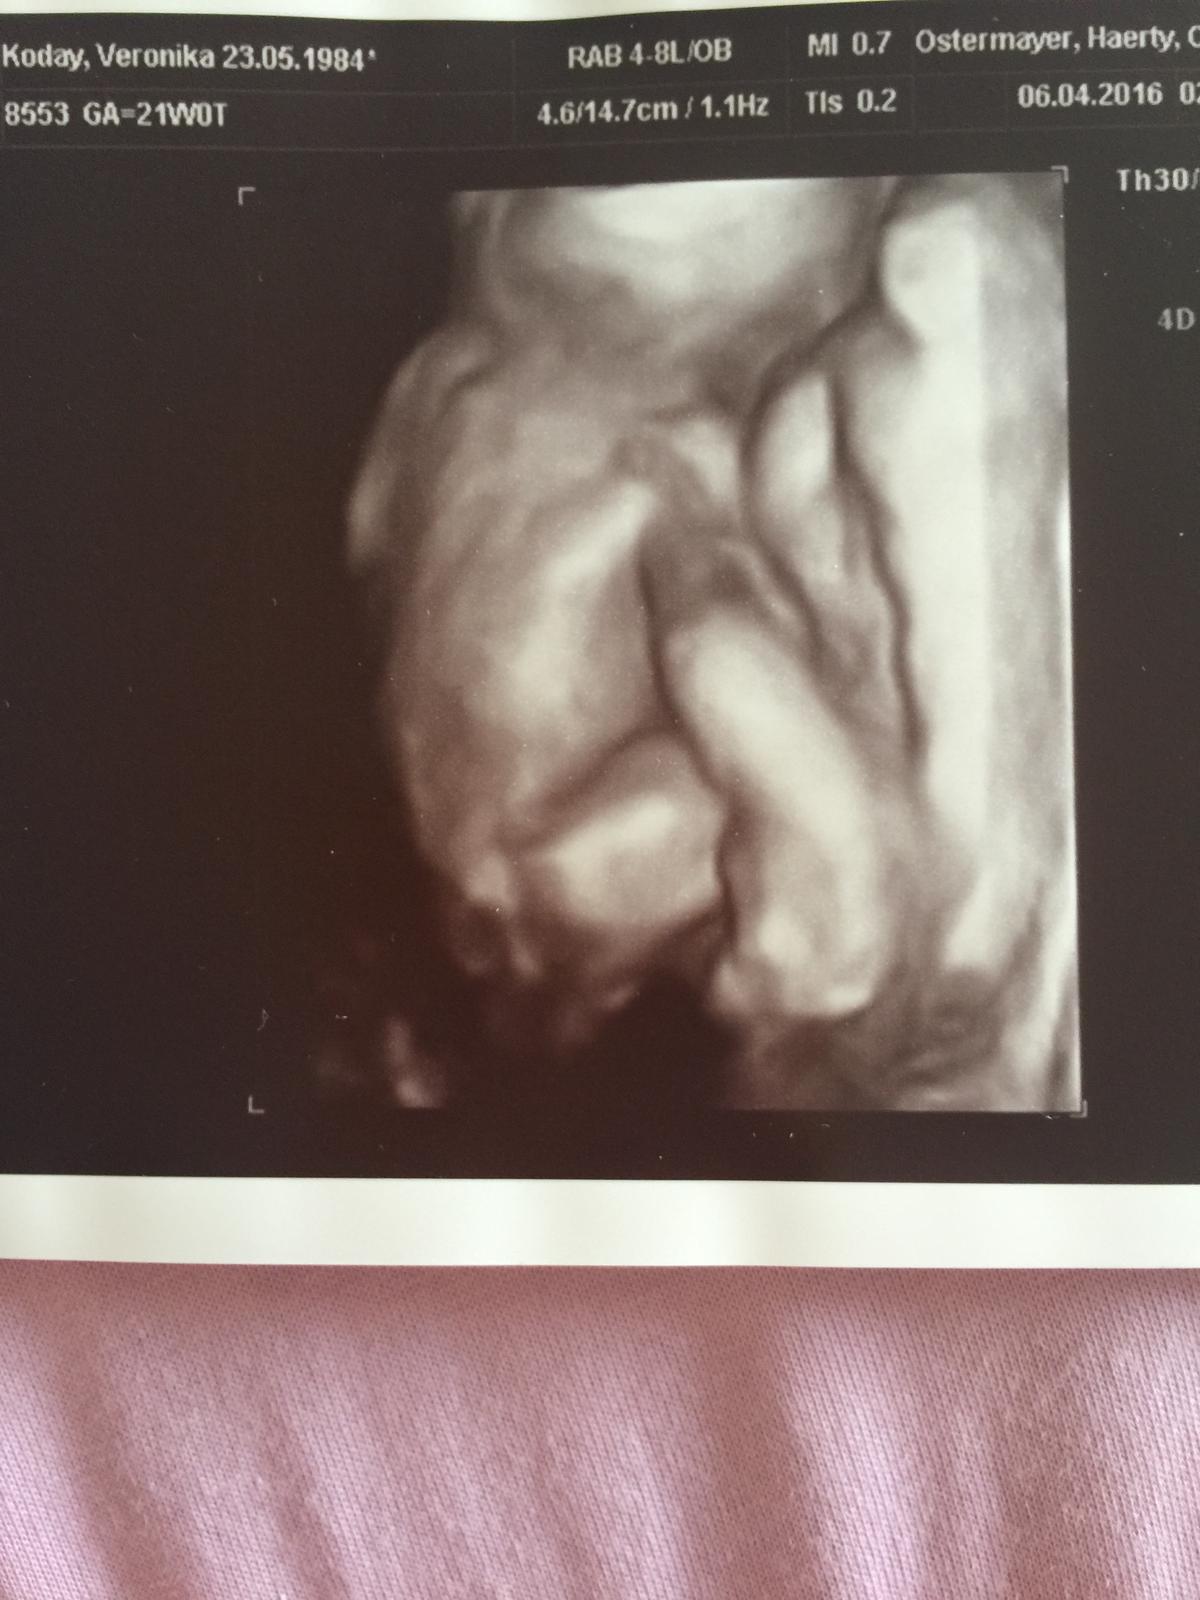

@lucianna1981 Ahojte tak u nás chvala panu bohu vsetko v poriadku.Prave som prišla z poradne .Cakame krásneho chlapčeka .Som velmi šťastná.Dievcata prajem aby aj u vás bolo vsetko uz len dobre.😘

@lucianna1981 nás chrustik